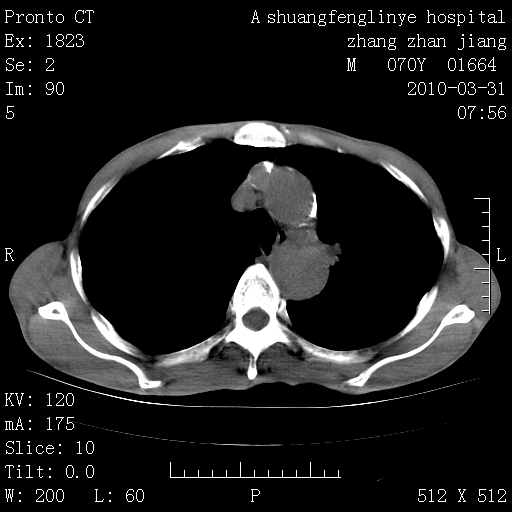

双上肺继发型tb并左上空洞形成,主动脉冠脉钙化。

1)两肺上叶继发性肺结核并左肺上叶空洞形成。2)冠状动脉及主动脉钙化。